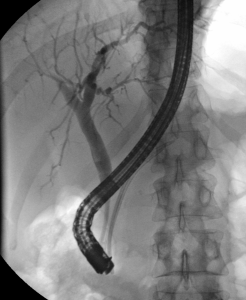

Vyšetření žlučových cest – ERCP (endoskopická retrográdní cholangiopankreatikografie)

ERCP je diagnostická a terapeutická metoda. Kombinuje v sobě endoskopické a radiologické vyšetření. Jejím cílem je zobrazit žlučové cesty a a v případě potřeby také vývody pankreatu. Vyšetření se provádí pod vedením gastroenterologa na radiologickém oddělení.

Využíváme C-rameno Multidiagnost Eleva od firmy Philips, digitální zpracování a archivaci nálezů.

V dohledné době očekáváme zakoupení nového skiaskopického kompletu a kompletní přesun vyšetřovny na gastroenterologické oddělení. Provádíme papilotomie, stentáže (plastovými i metalickými stenty), dilatace stenóz žluč. cest, extrakce konkrementů, jejich drcení (mechanickou litotrypsi), vyšetření žlučových i pankreatických cest cytologické a kultivační, nově i endoskopicky, urgentní výkony – zejména při zánětech žluč. cest či slinivky.

Vyšetření se provádí za hospitalizace. Pacient je před vyšetřením informován o jeho průběhu a podepisuje informovaný souhlas. Vyšetření tvá asi 15 až 45 minut, dle rozsahu výkonu. Pacient je v jeho průběhu v poloze na levém boku. Pacientovi se před vyšetřením aplikuje do oblasti kořene jazyka lokální znecitlivění (anestetikum) a do žíly zklidňující léky. V některých případech se preventivně podávají i antibiotika. Lékař následně zavede ústy endoskop (tenkou flexibilní trubici s optikou), pokračuje přes jícen, žaludek až do dvanáctníku, kde nalezne ústí žlučových cest a vývodu pankreatu, tzv. Vaterskou papilu. Poté lékař vysune z endoskopu tenkou sondu, pomocí níž vstříkne kontrastní látku, která zobrazí dle potřeby žlučové cesty nebo vývod slinivky. V této části vyšetření se provede několik rentgenových snímků. Pomocí metody ERCP je možné odstranění konkrementu, rozšíření zúžení žlučových cest či zavádění drénů. Podle potřeby je možné provést biopsii (odběr malého kousku tkáně k histologickému vyšetření).

Co nám vyšetření ukáže?

Toto invazivní vyšetření poskytuje lékařům informaci o stavu žlučových cest a vývodů pankreatu. Na pořízených RTG snímcích mohou být patrná zúžení či úplná neprůchodnost některých jejich částí, které mohou být (kromě jiného) způsobeny i nádorem žlučových cest či pankreatu. V současné době je ERCP často prováděno s terapeutickým cílem.